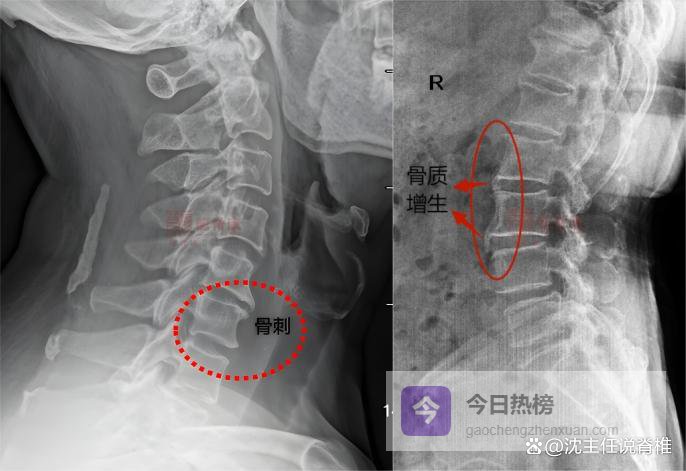

骨质增生是什么?骨质增生,俗称 “骨刺”,指骨头关节、边缘等部位因长期力学刺激,出现骨骼增生、骨赘形成的现象。颈椎、腰椎、足跟、膝关节等等全身骨头关节处,都有可能出现骨质增生。

腰椎骨质增生即是长在腰椎上的骨刺,是腰椎退行性病变的常见表现。